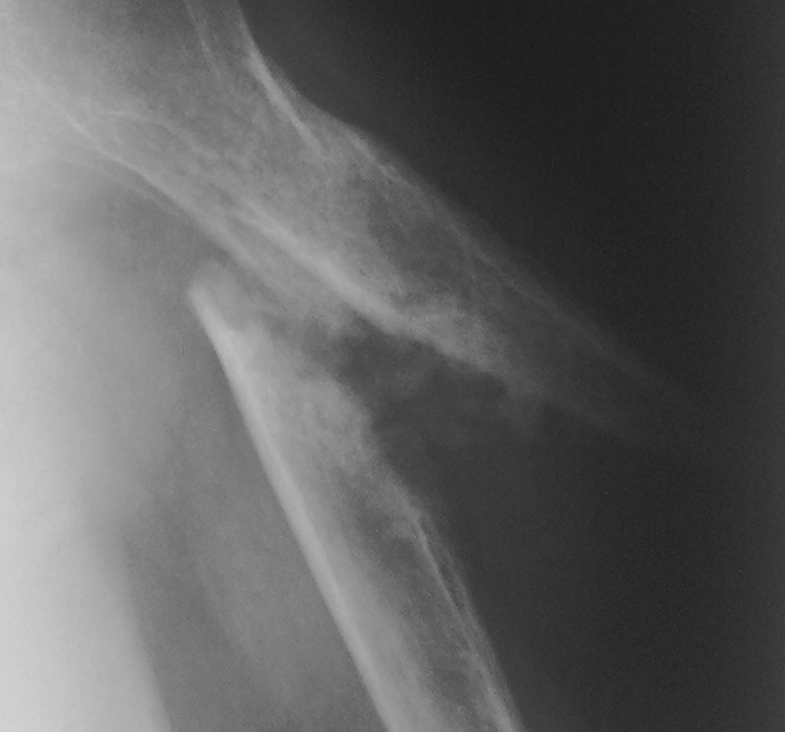

Итак, снимки, представленные, "как первые", т.е. после "свершившегося перелома".

Перелом косой, с некоторым захождением и с некоторым смещением под углом, ну а соответственно по ширине. Возможна некоторая ротация, конечно плохо, что не видно дистального эпифиза плечевой кости, Но "линия разлома" демонстрирует "конгруентность отломков", пусть на меня не обидятся за термин "конгруентность отломков" и отсутсвие осколков. Следовательно, нужно предрположить, что при адекватной репозиции "сращение" не представляло, каких либо проблем.

Область ключично-акромиального сочленения, по всей видимости, в "возрастных рамках".